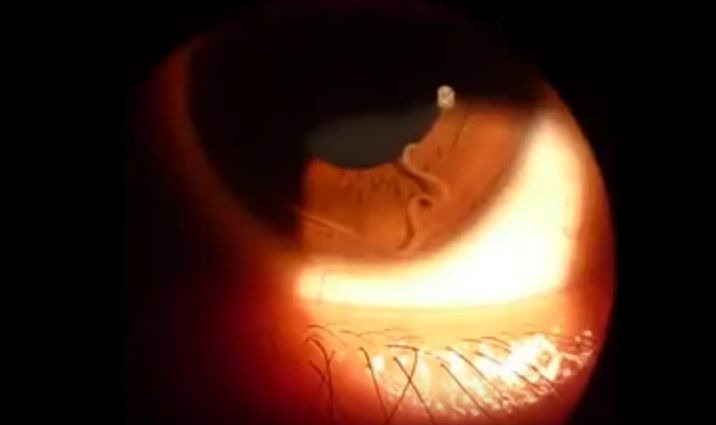

Filariozia Loa-loa este o boala care se manifesta prin prezenta în organismul uman a unei larve pentru aproximativ cinci sau 12 luni, timp în care se dezvolta. Cand ajunge la maturitate, parazitul elimina microfilarii care ajung în sange, urina si la nivelul plamanilor.

Viermii adulti au tendinta de a se deplasa la nivelul globului ocular, moment în care vederea se încetosaza. Boala este prezenta în 10 tari aflate pe teritoriul Africii Centrale si Africii de Vest.